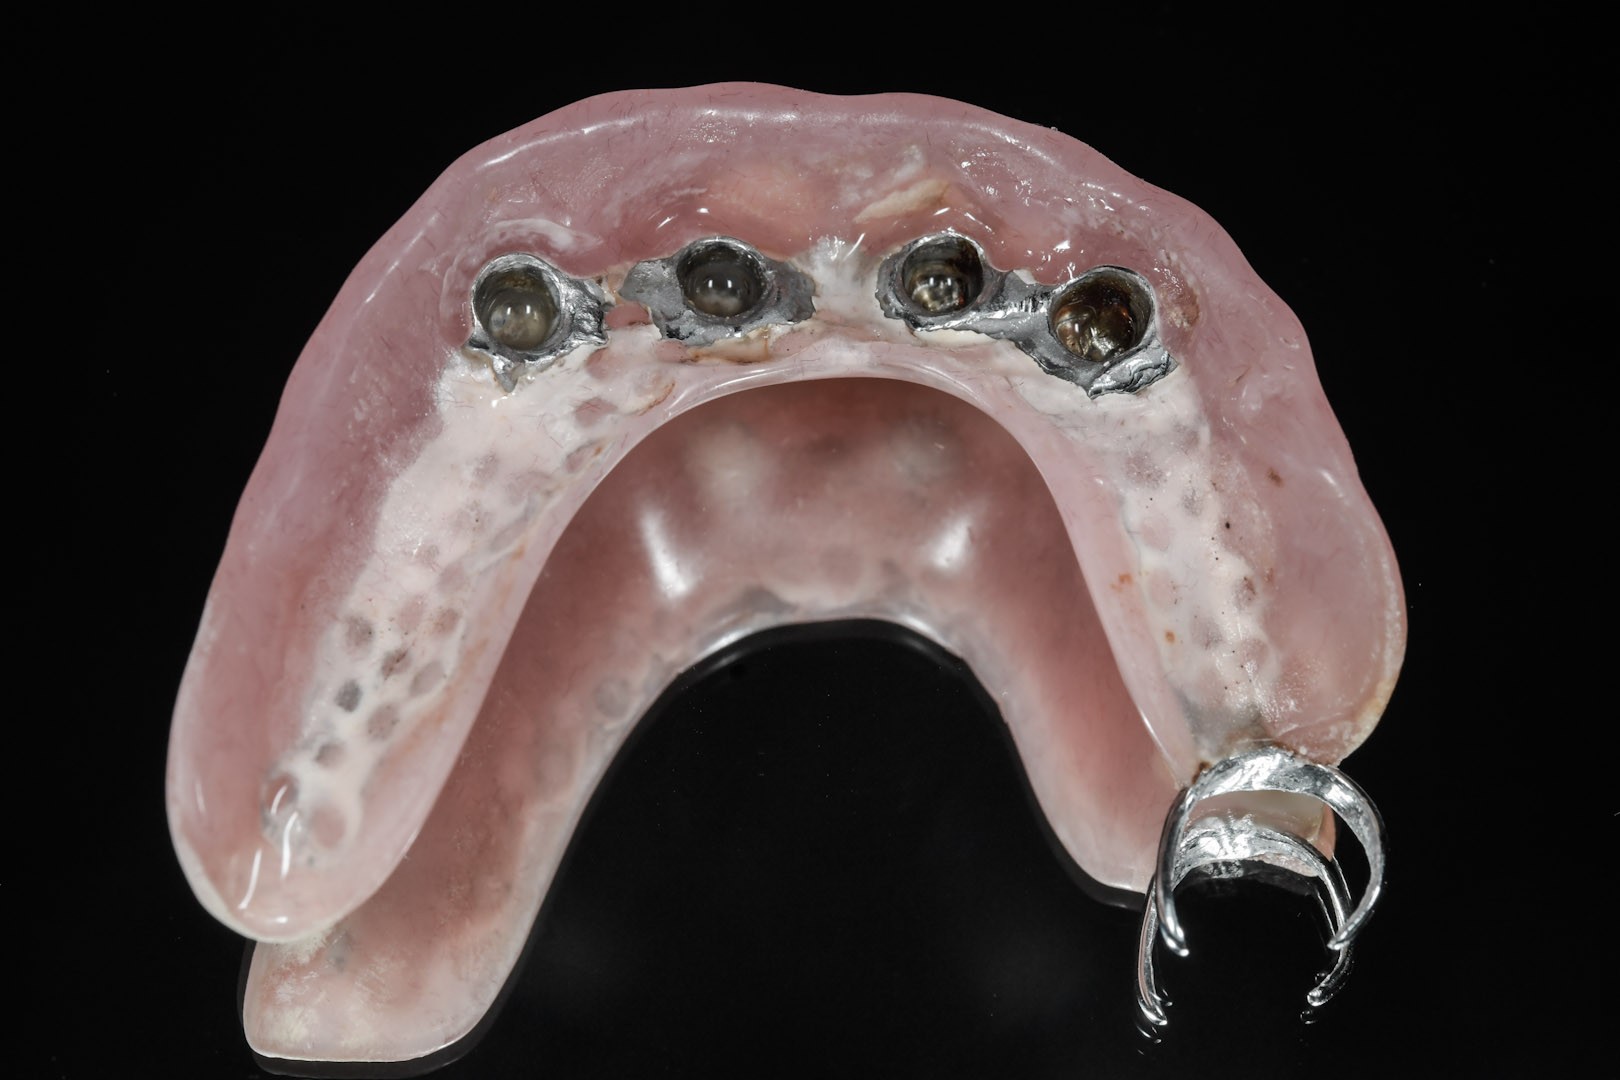

Protezy Overdenture, czyli nakładowe

Są pośrednim rozwiązaniem pomiędzy ruchomymi protezami osiadającymi a na stałe montowanymi na implantach mostami. To również ruchome protezy o zredukowanej płycie, których zasada działania polega na tym, że są częściowo wsparte na implantach.

Zazwyczaj umocowuje je do podłoża od 2 do 4 wszczepionych implantów, dla których optymalną pozycją jest przednia część wyrostka zębodołowego szczęk lub żuchwy.

Za stabilizację pomiędzy płytą protezy nakładowej a wszczepami odpowiedzialne są różnego typu odpowiadające sobie elementy retencyjne. Z jednej strony przytwierdzone są do szyjek implantów, z drugiej – do płyty protezy Overdenture.

Ze względu na rodzaj zastosowanych elementów zaczepowych istnieje kilka sposobów stabilizacji protez na implantach:

Dla umocowania protez Overdenture można użyć każdego typu implantów, dopasowując do nich standardowe elementy zaczepowe dla protez lub wykonać indywidualne w laboratorium. Istnieją także rozwiązania systemowe, które uwzględniają zastosowanie specjalnych implantów przeznaczonych tylko dla podparcia protez ruchomych. Tego typu implanty nie mogą być opcjonalnie wykorzystywane jako filary dla mostów mocowanych na stałe w przypadku zmiany koncepcji protetycznej, która polega na wprowadzeniu dodatkowej i wymaganej ilości wszczepów dla przykręcenia do nich stabilnych prac protetycznych.

Zaletą rozwiązań systemowych dla protez Overdenture jest cena oraz pełna kompatybilność implantów i uzupełnień protetycznych, które są stworzone i przeznaczone dokładnie dla siebie.

Protezy Overdenture (nakładowe) to ruchome uzupełnienia protetyczne, które dla podparcia i stabilizacji w jamie ustnej wykorzystują wszczepione uprzednio implanty. Niezbędna do prawidłowej konstrukcji takiej protezy ilość implantów to 2–4. Zaletą protez Overdenture jest niewątpliwie możliwość redukcji płyty protezy i lepsza jej stabilizacja dzięki elementom retencyjnym przytwierdzonym z jednej strony do implantu, a z drugiej do płyty protezy. Ze względu na rodzaj zastosowanych w nich elementów retencyjnych wyróżnia się zespolenia typu locator, kulkowe, belki Doldera, połączenia teleskopowe, magnesy i mieszane (różne zespolenia).

Ważnymi aspektami zastosowania protez Overdenture jest ich dobra stabilizacja w porównaniu z protezami całkowitymi zakładanymi do jamy ustnej bez wszczepiania implantów oraz zahamowanie procesu resorpcji kości i wyrostka zębodołowego.